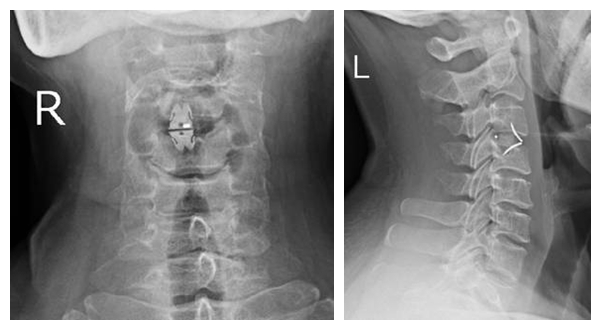

術(shù)后DR

劉女士及家屬商量后決定行手術(shù)予轉(zhuǎn)脊椎關(guān)節(jié)科。在脊椎關(guān)節(jié)科行頸椎前路頸3/4椎間盤摘除、椎管減壓、椎間植骨融合內(nèi)固定術(shù)。術(shù)后予預(yù)防感染、脫水消腫、營養(yǎng)神經(jīng)、抗炎等對癥支持治療?,F(xiàn)患者術(shù)后3周頸部及左上肢疼痛癥狀完全消失,雙上肢無不適,可安靜入睡,四肢肌力、肌張力正常。